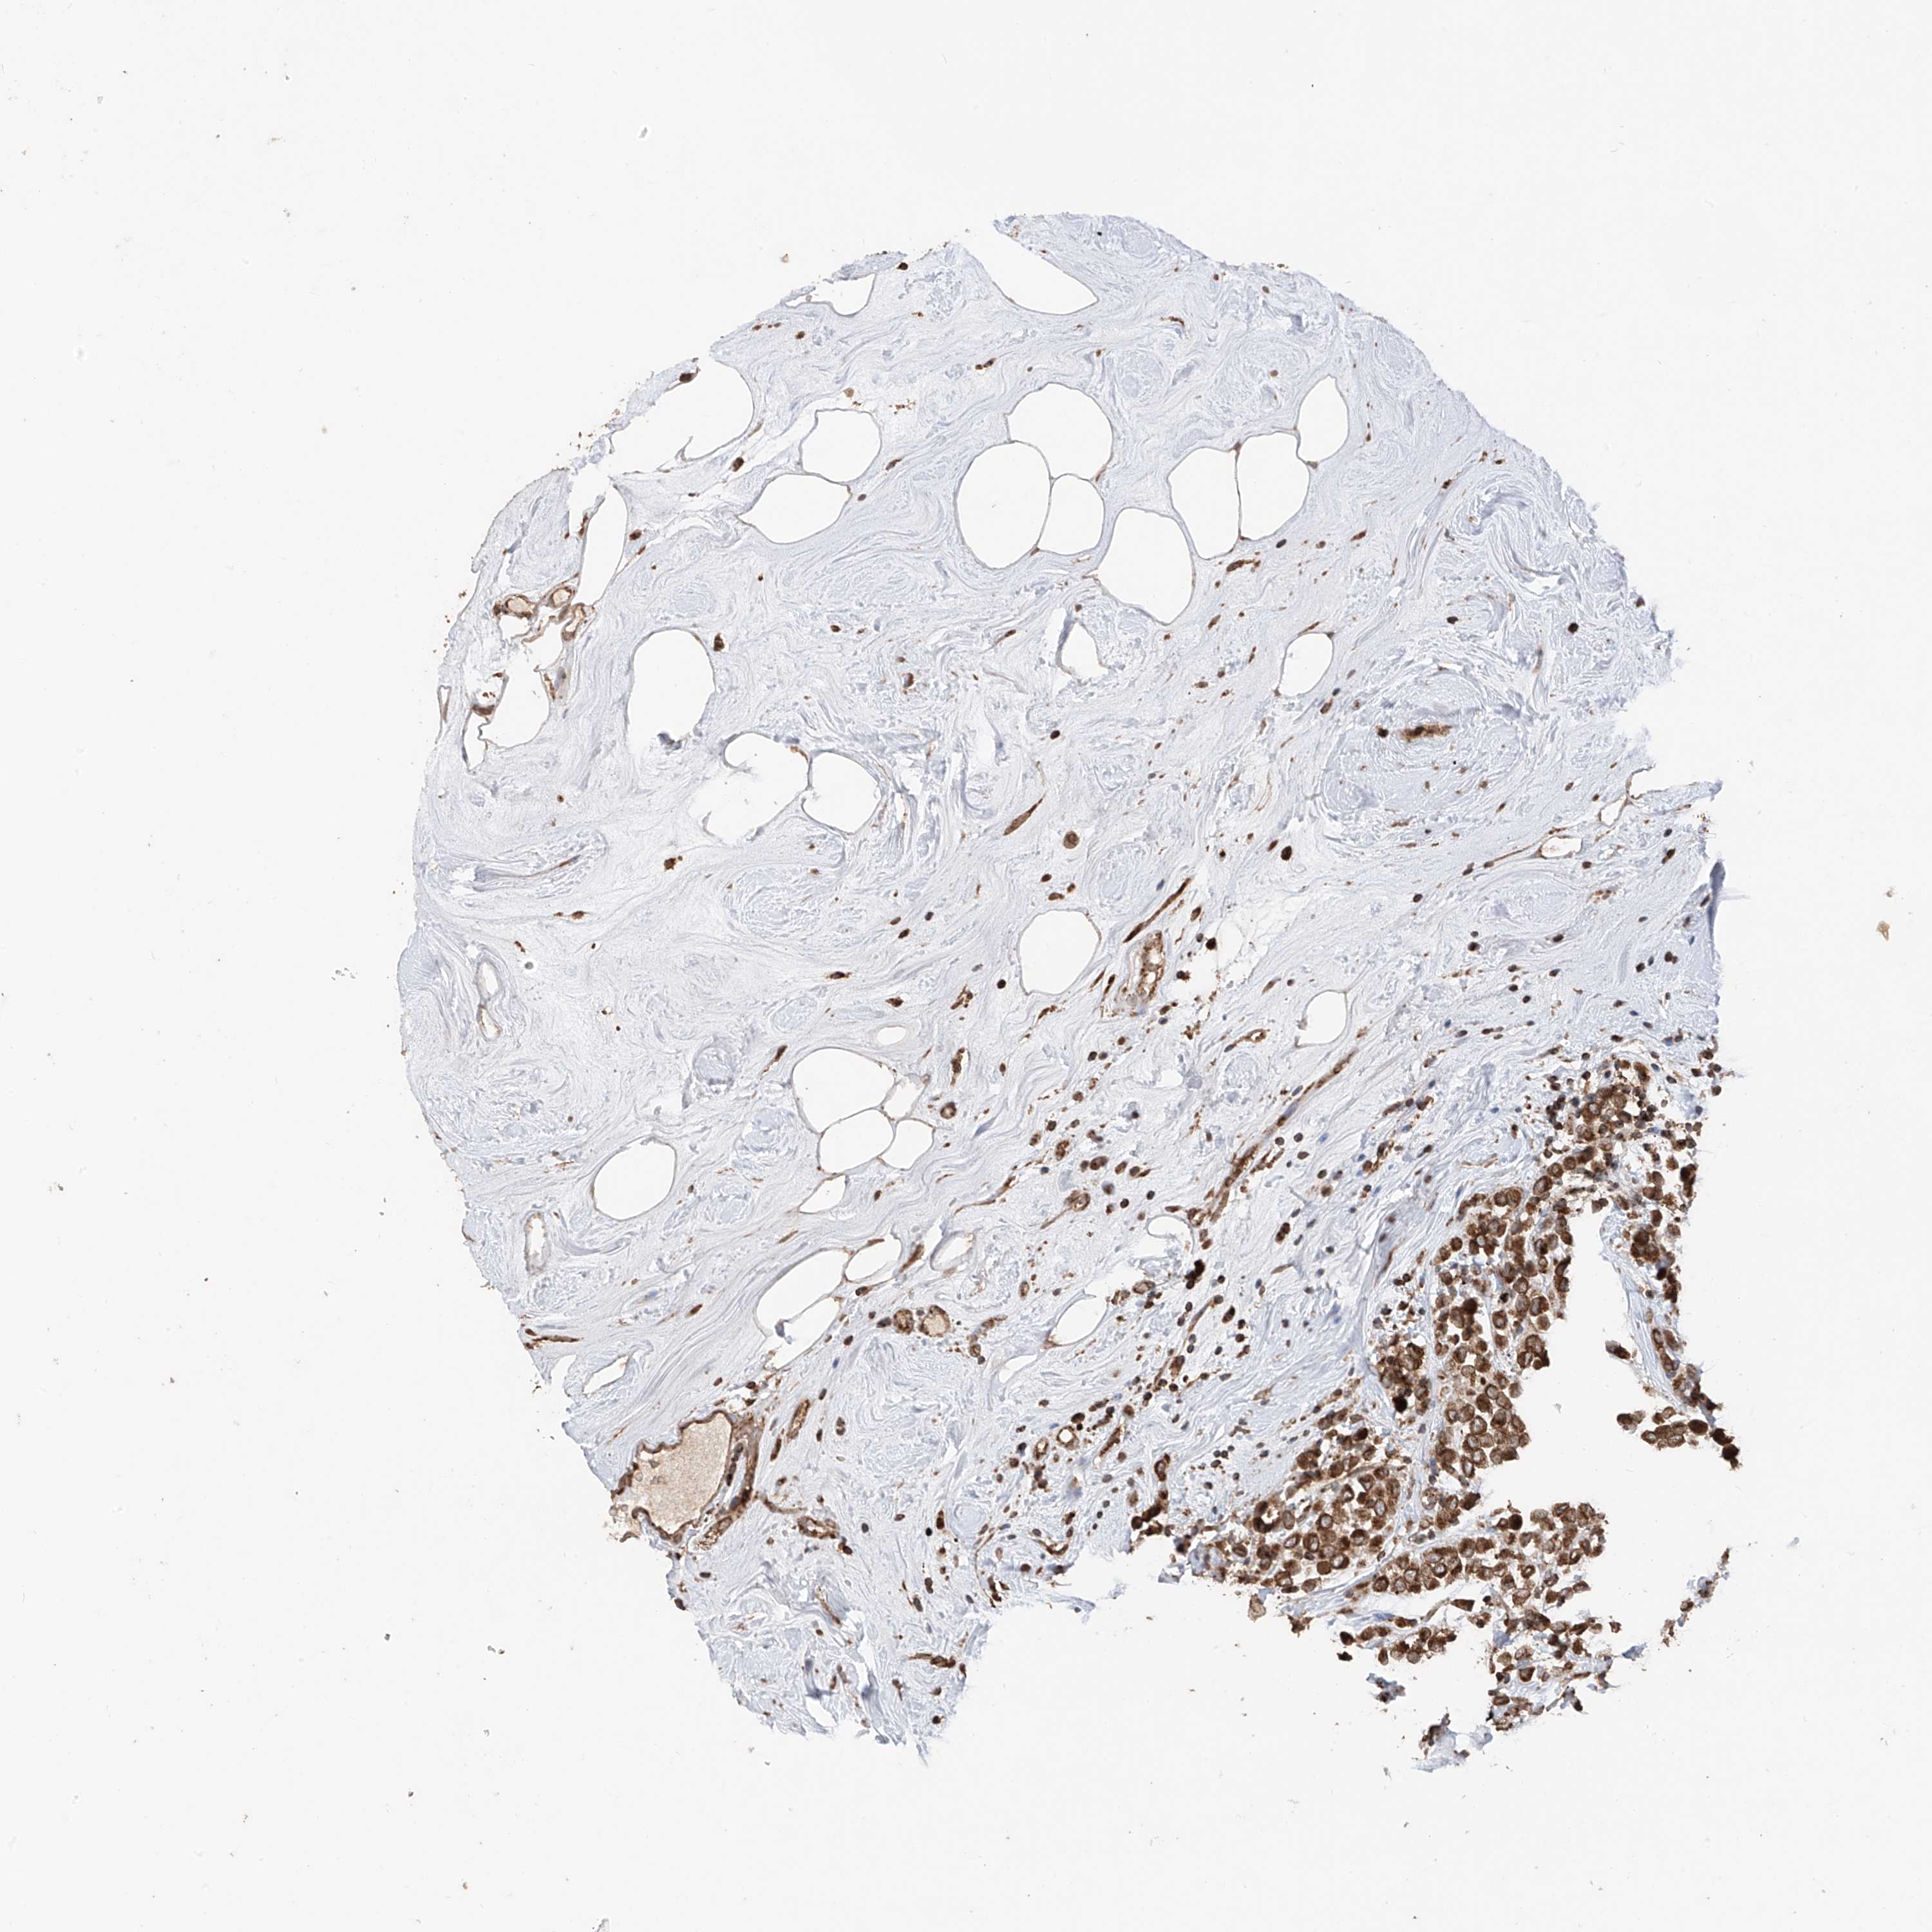

CANCER BREAST CANCER Show tissue menu

BRCA TCGA BRCA VALIDATION PROTEIN EXPRESSION

AHCTF1 is not prognostic in Breast Invasive Carcinoma (TCGA)